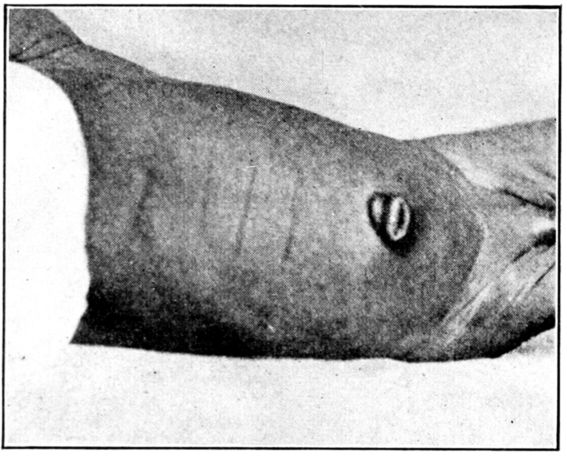

| 151. | Umbilicus immediately after separation of cord | 458 |

| 152. | Well healed umbilicus | 458 |